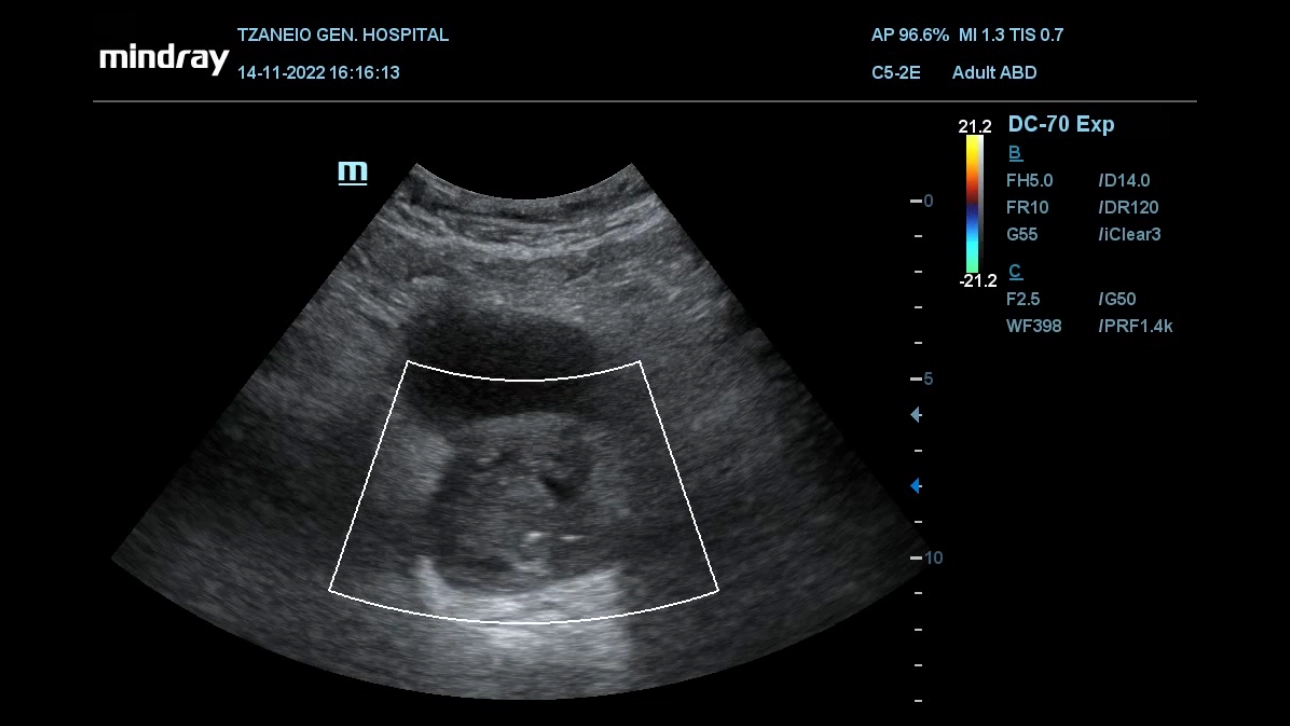

Finally, the authors utilize transabdominal US for non-invasive, dynamic study of urination in selected patients who experience symptomatic recurrence post PAE [9]. Interestingly, in a few of these patients, necrosis and degeneration of prostatic tissue post PAE, results in freely mobile prostatic remnants that intermittently protrude in the bladder outlet and/or in the urethra and block urine flow (Fig 4).

Figure4: Dynamic transabdominal US study in patient experiencing symptomatic recurrence post PAE. Ovoid, degenerated prostatic tissue (asterisk in both images) moves into prostatic urethra, intermittently interrupting urinary flow. A: The position of the degenerated tissue permits some urinary flow (indicated by the doppler signal) during patient’s attempt to urinate. B: The degenerated tissue has now changed position in the prostatic urethra (arrow indicates direction of movement) and urinary flow is now blocked. (video also available)